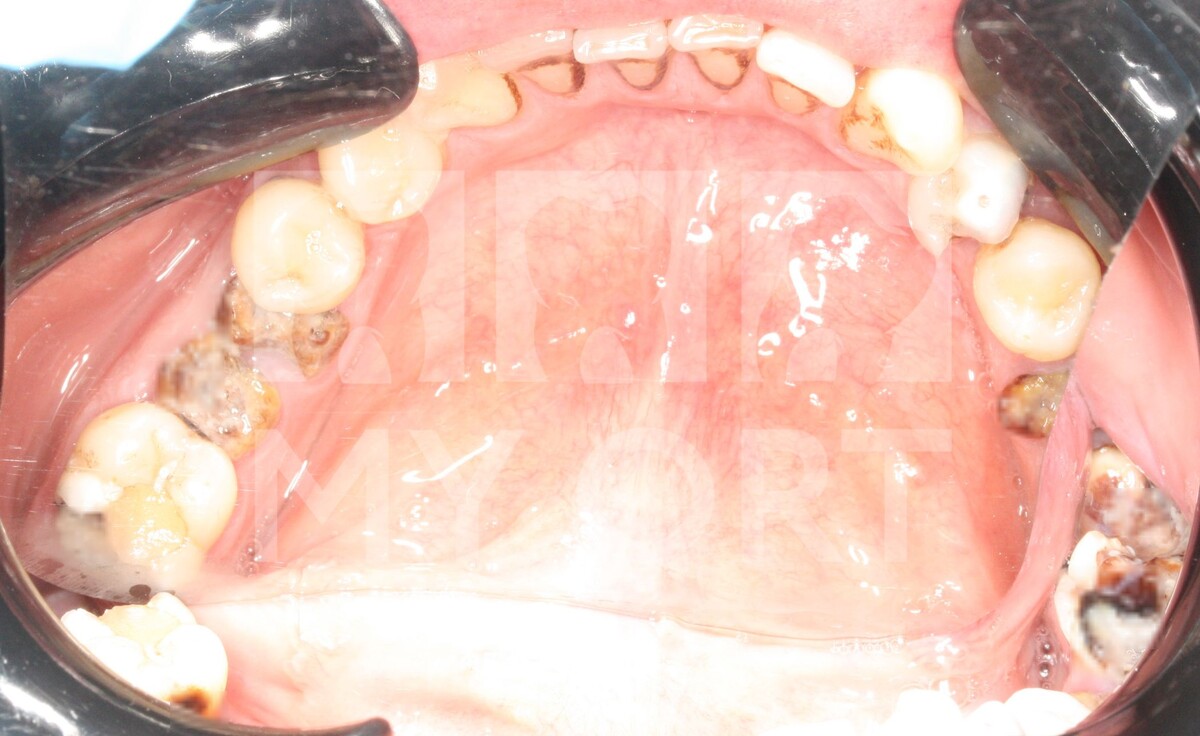

При осмотре полости рта и проведении полной диагностики были определены множественные корни разрушенных зубов, не подлежащих восстановлению.

ДО лечения:

-9